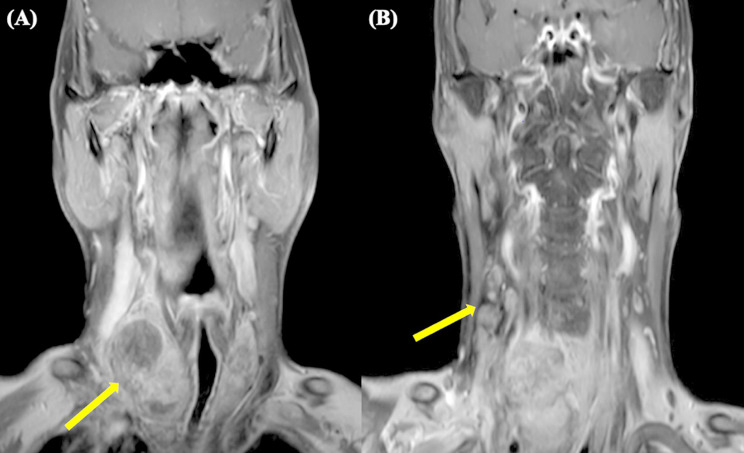

Background: Thyroid angiosarcoma is a rare, highly aggressive malignancy of endothelial origin, characterized by rapid growth, invasive behavior, and a high metastatic potential. While most cases are reported from the Alpine regions of Europe, its occurrence elsewhere is exceedingly rare. The aim of our review is to report a case of thyroid angiosarcoma and provide a systematic review of the literature, focusing on clinical presentation, diagnostic strategies, and treatment outcomes.

Results: A systematic review of 72 cases of thyroid angiosarcoma reported in 52 articles was conducted. The median patient age was 66 years, with female predominance (4:3). Most patients presented with a rapidly enlarging thyroid mass and compressive symptoms. Diagnosis required a combination of histopathology and radiologic imaging, with Fine Needle Aspiration Cytology as the initial tool in 47% of patients. Total thyroidectomy was performed in 67% of cases, and 42% of patients received adjuvant therapies. The prognosis remains poor, with a median overall survival of 28 months and a 3-year survival rate of 40%.